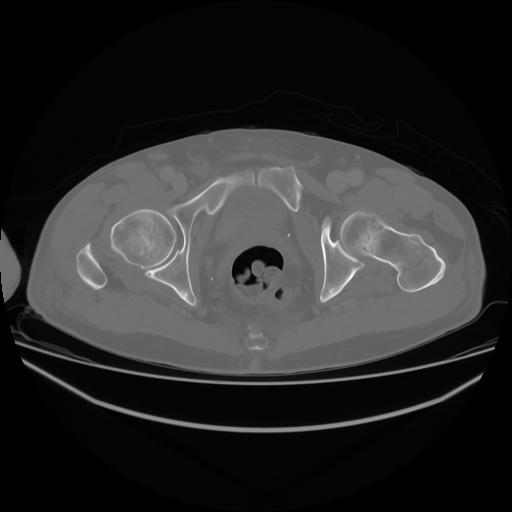

4 CUERPO,CE,Axial,3.0,CUERPO,,